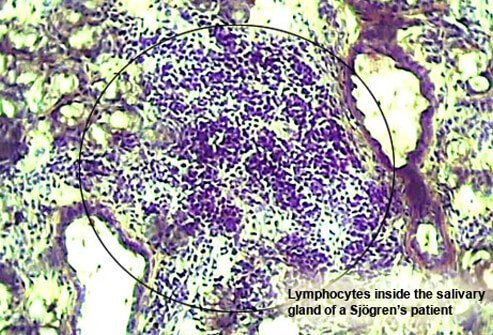

Sjögren’s Syndrome and Other Medical Causes

Sometimes disease causes xerostomia. A health condition known as Sjögren's (SHOW-grens) syndrome can cause white blood cells to attack the tear and salivary glands. This can dry out the eyes and mouth. It affects an estimated 400,000 to 3.1 million adults. Older women are particularly susceptible.

With Sjögren’s syndrome, patients remain otherwise healthy, but may find their mouths are dry, and may also experience swollen glands around the face and neck, irritated, gritty-feeling eyes and dryness in nasal passages, throat, and vagina. Acid reflux may also accompany this inflammatory disease.